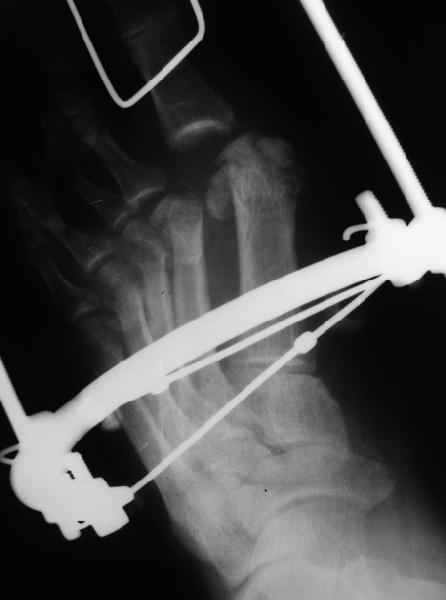

1 передний отдел стопы делается в косой, а не боковой проекции - на боковой все плюсневые кости накладываются друг на друга, и ничего не видно - это же аксиоматично! Я, например, на прямых проекциях не вижу совсем признаков перелома первой и четвертой плюсневой, и сомневаюсь в переломе третьей, боковые же совершенно неинформативны.

Они же наложили дистракционный аппарат (вместо того, чтоб сделать открытое вправление зафиксировать это одной спицой Киршнера), продержали больного две недели в аппарате (ЗАЧЕМ?), а теперь спрашивают , что делать...

По поводу остеотомии Вейля - в ДАННОМ случае мы уже создали запас тканей дистракционным аппаратом.

Имеем - без малого двухмесячные переломовывихи перeднего отдела стопы , больной в отделении 20 дней, доктор думает, что ему делать:

1 полное смещение второй плюсневой, которое НАВЕРНЯКА приведет к появлению натоптыша и невозможности нагружать передний отдел стопы - всеми участниками просто игнорируется.